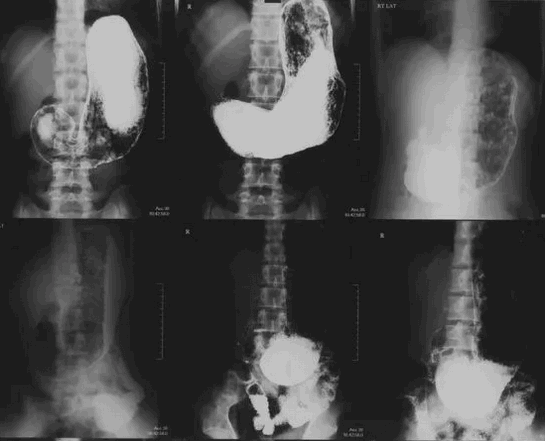

На контрастном снимке видно, что кардиа, свод и тело желудка образуют нисходящую часть тени, а пилорическая часть желудка — восходящую часть тени (рис. 126, 127). Соотношения нисходящей и восходящей частей тени желудка у разных людей неодинаковы; можно наблюдать три основных формы и положения желудка.

1. Желудок в форме рога (рис. 128). Тело желудка расположено почти поперек, постепенно суживаясь к пилорической части. Привратник лежит вправо от правого края позвоночного столба и является самой низкой точкой желудка. Вследствие этого угол между нисходящей и восходящей частями желудка отсутствует. Весь желудок расположен почти поперечно.

2. Желудок в форме крючка (рис. 129). Нисходящая часть желудка спускается косо или почти отвесно вниз. Восходящая часть расположена косо — снизу вверх и направо. Привратник лежит у правого края позвоночного столба. Между восходящей и нисходящей частями образуется угол (incisura angularis), несколько меньший прямого. Общее положение желудка косое.

3. Желудок в форме чулка, или удлиненный желудок. Он похож на предыдущий («крючок»), но имеет некоторые отличия: как говорит само название, нисходящая часть его более удлинена и спускается вертикально; восходящая часть поднимается вверх круче, чем у желудка в форме крючка. Угол, образуемый малой кривизной, более острый (30 — 40°). Весь желудок расположен влево от срединной линии и лишь незначительно переходит за нее. Общее положение желудка вертикальное.

Таким образом, между формой и положением желудка отмечается корреляция: желудок в форме рога имеет чаще поперечное положение, желудок в форме крючка — косое, удлиненный желудок — вертикальное положение.

Сначала обычно делают обзорную рентгенограмму брюшной полости в положении стоя. Она помогает сразу выявить грубые нарушения функционирования желудочно-кишечного тракта.

При проведении рентгеноскопии желудка с барием пациент в процессе исследования дробно пьет 200мл контрастного вещества , которое имеет цвет и консистенцию сметаны, а вкус мела.

Затем выполняют снимки. Пациента просят принимать разные положения: стоя, лежа на спине, на животе, на правом и левом боку, в положении лежа на спине с приподнятым ножным концом (положение Тренделенбурга). Так контраст равномерно заполняет желудок, контурируются разные стенки органа.